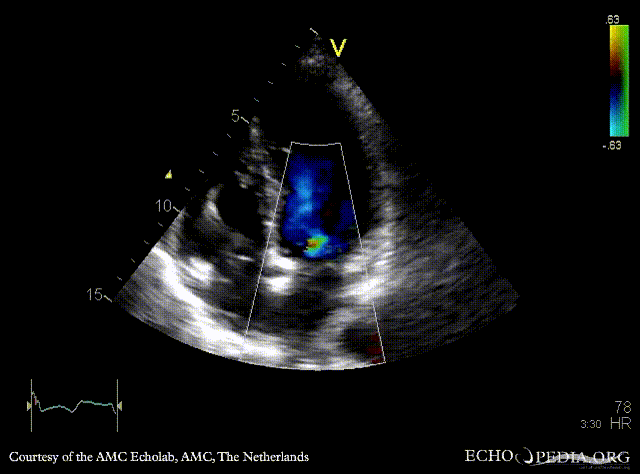

E00502.gif E00503.gif

PLAX: concentric hypertrophy of left ventricle, SAM of AMVL PLAX with Color Doppler: high velocity turbulent flow in LVOT